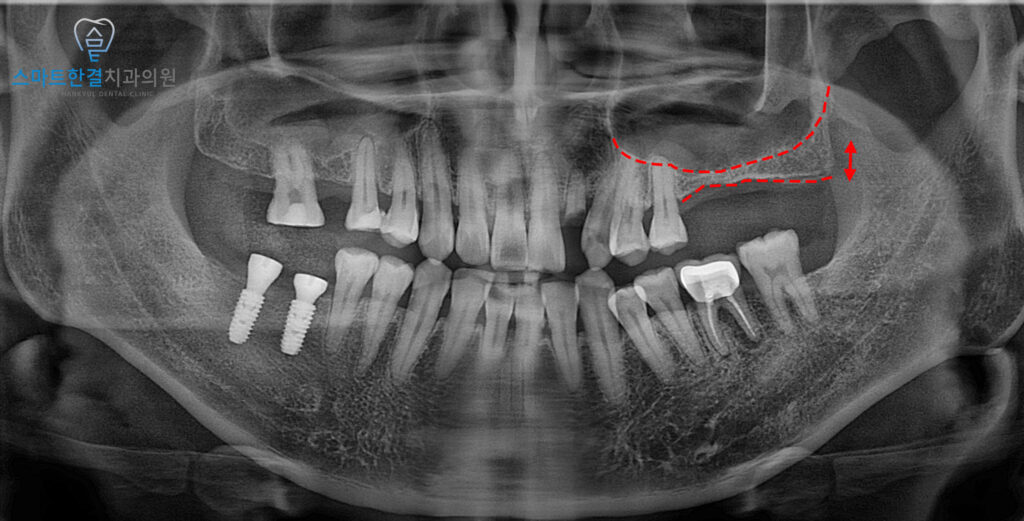

환자분처럼 뼈의 높이가 많이 부족한 경우에는

치조정 접근만으로는 한계가 있기 때문에,

측방으로 접근하는 방법을 통해

상악동을 들어 올리고 인공뼈를

이식하는 과정이 필요했어요.

그래서 본원에서는 상악동거상술을 진행하여

충분한 뼈의 공간을 확보한 뒤,

안정적으로 임플란트를 식립할 수 있도록

계획을 수립했답니다.